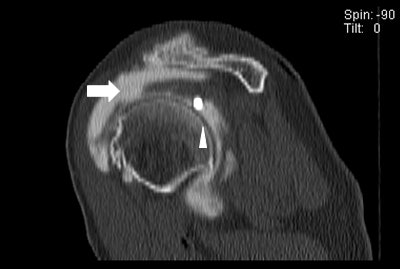

Nineteen patients underwent additional imaging with CT arthrography because metallic artifacts precluded an MRI assessment of their shoulder pathology. CT arthrography found four anterior labral tears, three posterior labral tears, two SLAP tears, and one supraspinatus tendon tear.

Magee noted two significant outcomes of the study. The first is that MR arthrography appears to be superior to conventional MRI in detecting labral tears and supraspinatus tendon tears. The second is that CT can be essential to making the diagnosis when there is a metallic artifact.

While he is not an orthopedic surgeon, Magee said the latter conclusion is particularly significant given the rise in the use of metallic objects and implants, which can repair injured shoulders better than some older, plastic fixation devices.

"Some shoulder surgeons are starting to move toward ordering a CT arthrogram instead of an MRI," he said. "Some of the advances in CT have made the modality very good at detecting pathology in the musculoskeletal system. We have 64-detetctor-row CT that reconstructs very well with very thin [slice] imaging. It provides a good alternative to MRI."